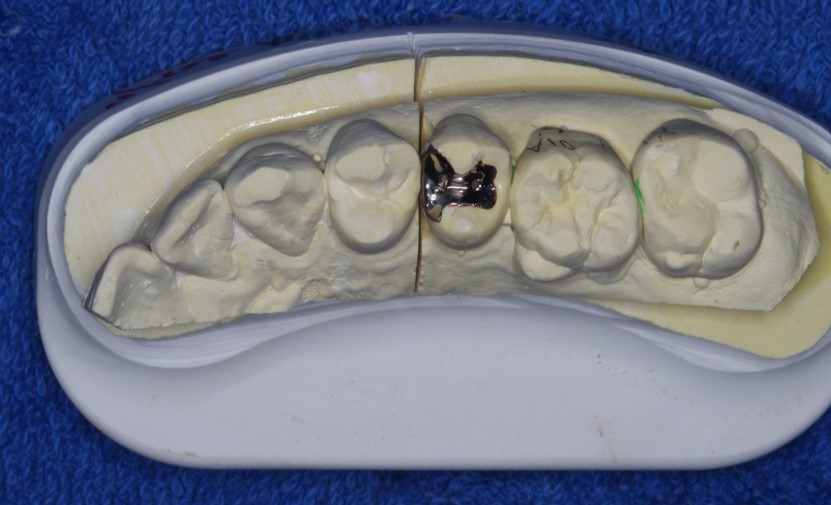

むし歯がある程度大きくなると、レジンと言われるプラスティックの樹脂でつめるのでは、二次的なむし歯にばりやすく強度が弱いため

歯型をとり上の図のような「インレー」とよばれるつめものを入れることになります。

歯型を取り、インレーを作り接着材を用いることでこの隙間ができにくくするといった考え方です。

実際に上の写真のものをお口の中につめた写真が下になります。